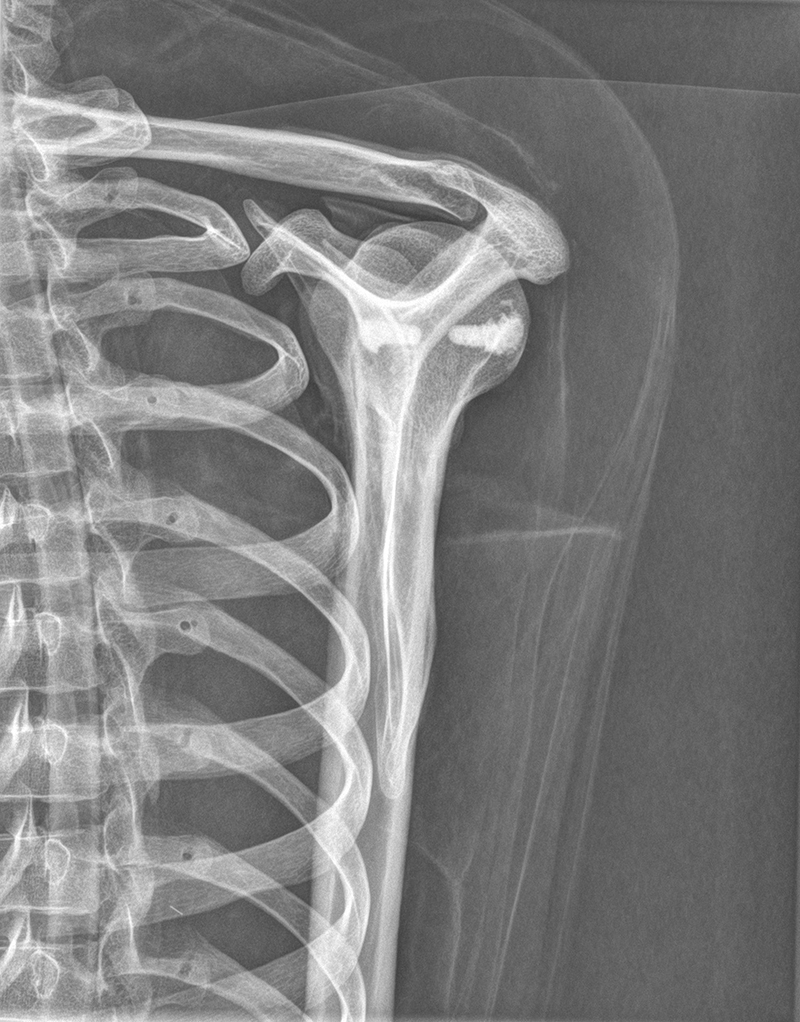

Dieses weltweit einmalige Phantom bietet erstklassige Übungsmöglichkeiten für die Lagerungs- und Einstelltechnik in der Projektions-Radiographie und gehört eigentlich zur Grundausstattung jeder Röntgen-Ausbildungsstätte. Das Phantom enthält ein natürliches menschliches Skelett sowie die Umrisse von Kehlkopf, Lunge, Herz und Nieren (Organe erscheinen als Schatten auf den Röntgenbildern), dadurch können mit dem Phantom echte Röntgenaufnahmen wie beim Patienten gemacht werden. Durch die Verwendung des echten Skeletts können Leitstrukturen im Knochen erkannt werden, was bei Kunststoffskeletten nicht möglich ist. Bei der Montage des Phantoms wird besonderer Wert auf die Darstellung der Gelenkspalte gelegt. Die Gelenke sind voll beweglich montiert, und ermöglichen die Lagerung in den normalen Röntgenpositionen (z.B. Froschposition, Pro- und Supination des Unterarms). Die Arme können nach oben bewegt werden, so dass das Modell auch für alle knöchernen Untersuchungen im CT verwendet werden kann. Bei jedem Phantom handelt es sich um ein handgefertigtes Unikat, welches sich in Größe und Ausführung unterscheiden kann. Je nach Modell können pathologische Befunde vorhanden sein, die äußere Erscheinung kann sich je nach Größe des Modells unterscheiden. Die neue Ausführung dieses Modells wurde in Zusammenarbeit mit einer namhaften deutschen Schule für Med. Techn. Radiologieassistenten komplett überarbeitet und erfüllt alle Anforderungen für die Ausbildung. Der Verkauf dieses Phantoms erfolgt nur gegen Nachweis der medizinischen Verwendung. Natürliche Größe.